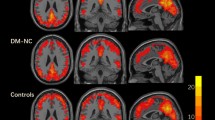

Compared with the HCs, the T2DM patients showed significantly higher activation in three fronto-parietal ICs after controlling for the effects of age, gender and education (IC19, t = 3.432, P = 0.001, effect size [ES] = 0.793; IC21, t = 2.901, P = 0.006, ES = 0.936; IC22, t = 3.115, P = 0.004, ES = 1.002; Bonferroni correction) (Fig. 3). To validate that these three ICs were activated by WM in both the T2DM patients and the HCs, we performed a traditional voxel-wise activation analysis. Based on this analysis, we found that the spatial distributions of WM-evoked activation in both the HCs and the T2DM patients was highly overlapped with that of the three ICs; moreover, the strength and spatial extent of WM-evoked activation in the T2DM group were stronger than those in the HCs groups (See Supplementary Figures S1 and S2). Furthermore, in the patients with T2DM, the activation amplitudes of IC19, IC21 and IC22 were significantly positively correlated with AVLT short-term memory scores; the activation amplitudes of IC19 and IC22 were significantly negatively correlated with the IES of the 1-back WM task and a trend of negative correlation was shown between the activation amplitudes of IC21 and the IES of the 1-back WM task (Fig. 4). There was no significant correlation between the activation amplitudes and the accuracy rate in WM performance in the T2DM patients and there was no significant correlation between the activation amplitudes and any WM indices in the HCs (P > 0.05). The correlations between activation amplitudes and FBG or HbA1c levels were not significant in the T2DM patients (P > 0.05).

In this study, we combined fMRI and ICA techniques to investigate changes in brain activation and FC in WM networks in complication-free T2DM patients as they performed a digital 1-back WM task. Significantly increased activation was identified in several WM-related fronto-parietal networks in the assessed T2DM patients and the activation amplitudes of these WM networks were significantly associated with WM performance. In contrast, significantly decreased FC within the visual network (IC 10), the left fronto-parietal network (IC 19) and the posterior parietal network (IC 21) as well as decreased FC between the right fronto-parietal network (IC 22) and the visual network (IC 10) were shown in the complication-free T2DM patients. These inverse alterations in brain activation and FCs in WM networks may provide new insights into the neural mechanisms underlying WM impairment in T2DM patients.

Compared with the HCs, the T2DM patients demonstrated hyper-activation within three WM-related fronto-parietal components (IC19, IC21 and IC22). The fronto-parietal regions have been indisputably associated with WM in normal subjects31,32. Furthermore, impairments in fronto-parietal regions are usually evident in T2DM patients. For example, previous structure-imaging studies have demonstrated that gray matter and white matter in fronto-parietal regions are damaged in T2DM patients8,33 and reduced regional cerebral blood flow has also been found in the fronto-parietal lobes of T2DM patients34. Our results were consistent with a recent study showing increased activation in the bilateral frontal cortices of newly diagnosed, complication-free, middle-aged T2DM patients as they performed digital n-back WM tasks21. However, our findings were not consistent with another study demonstrating decreased activation in the frontal cortexes of T2DM patients as they performed a digital n-back task19. This discrepancy is probably due to the variable characteristics of the assessed T2DM patients. In Chen’s study19, for example, complications were not controlled for in T2DM patients, while in both He’s study20 and the current study, only T2DM patients with no typical complications were enrolled.